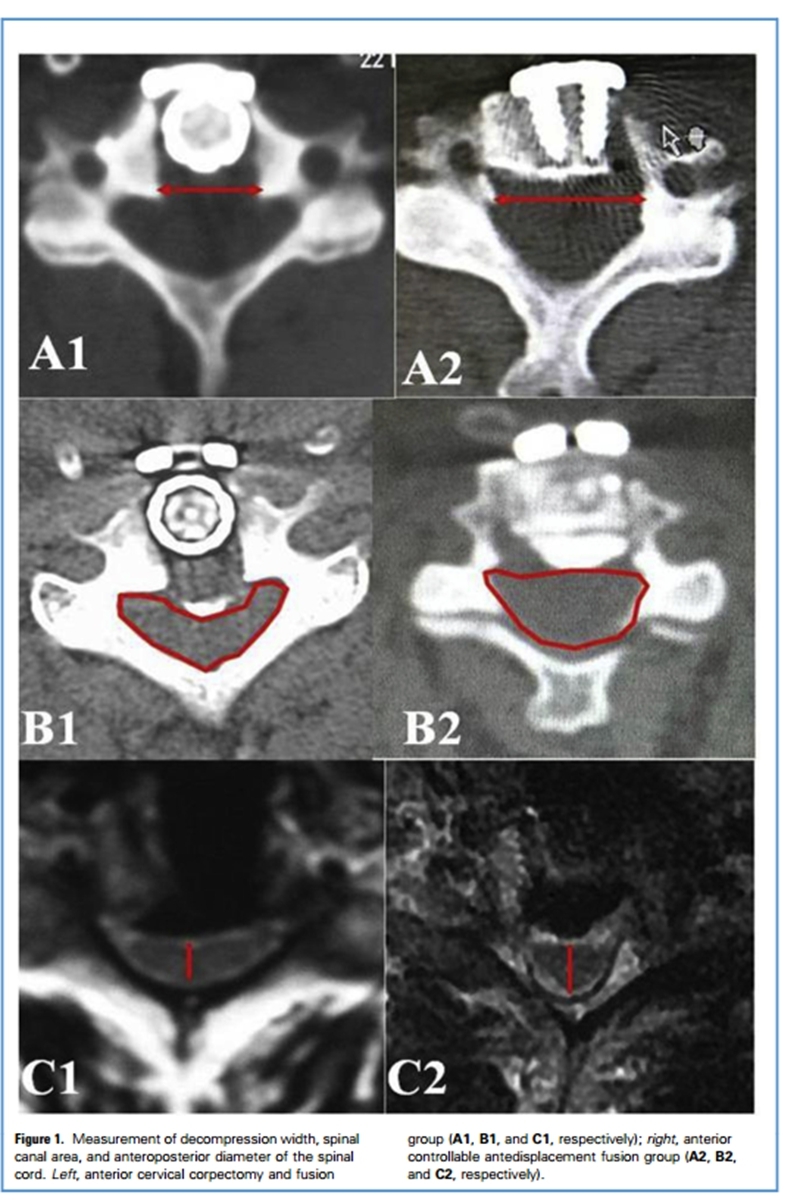

颈椎前路减压手术中,减压过窄易导致脊髓及神经根减压不彻底,减压过宽则可能伤及椎弓根和椎动脉。在ACAF手术中,两侧减压槽之间的宽度可达到18mm左右,宽于ACCF(anterior cervical corpectomy and fusion)手术。如此宽的减压范围,是否容易伤及椎动脉?术中是否有合适的解剖标志来帮助医生选择开槽位置?为了回答这一问题,长征医院脊柱二科孙璟川医生对影像解剖学进行研究。

通过回顾临床行ACAF手术患者的影像学资料,测量钩椎关节距椎弓根和椎动脉的距离等参数,我们发现:钩椎关节基底部距离两侧的椎动脉存在4.6-7.2mm的安全空间。

而在ACAF患者术后CT上测量两侧开槽的宽度、骨化物宽度后发现,将开槽位置定在钩椎关节基底部可将绝大多数骨化物包含在减压范围之内,即达到充分减压。该研究结果显示,使用钩椎关节的基底部作为ACAF手术中开槽的解剖标志可达到充分而安全的减压效果。

长征医院脊柱二科杨海松副教授对70例严重后纵韧带骨化症患者(34例行ACAF手术,36例行ACCF手术)的回顾性研究发现,ACAF技术的减压宽度范围显著宽于ACCF(17.9±1.0vs.15.1±0.8 mm)。ACAF组脊髓横截面积显著大于ACCF组(150.4±31.6vs.127.0±27.0mm2)ACAF组术后脊髓前后径恢复显著优于ACCF组(5.4±0.6vs.5.0±1.1mm)。术后6个月患者的神经功能恢复ACAF组显著优于ACCF组(6个月JOA评分15.4±0.9 vs.14.5±2.5分)。

研究将脊髓横截面形态分为回旋镖形、月牙形、三角形和圆柱形。研究发现,ACAF组患者术后脊髓形态恢复明显优于ACCF组,提示ACAF可提供更好的椎管扩大效果。